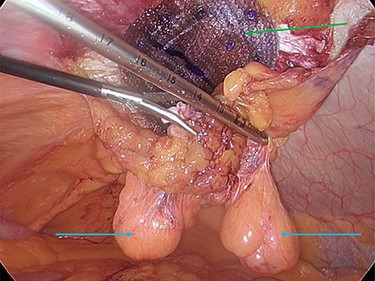

The hernia neck was closed with a 2-0 V-loc© suture (Fig. 5a and b), and a preperitoneal prolene mesh applied. The mesh was secured to the abdominal wall with an absorbable tack fixation device. The mesh was then reperitonealized with absorbable tackers (Fig. 6).

Preperitoneal mesh insertion (green arrow) and visible parietal peritoneal lipomas (blue arrows).

The decision was taken intraoperatively to leave the lipomas in situ as the hernia neck had been repaired, and it was thought that they could no longer cause any issue with pain or possible hernial reincarceration (Fig. 7).

The hernia neck was initially closed with an absorbable suture and a preperitoneal mesh applied. The mesh was then reperitonealized and the lipomas remained exterior to this. It was felt that the lipomas posed no further risk to incarceration, given the hernial neck closure and application of a preperitoneal mesh, so they were left in situ.